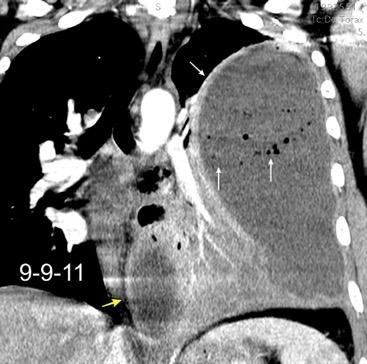

Absceso secundario a perforación de carcinoma. 3-4%. En flexura esplénica puede tener absceso subfrénico o empiema.

Empiema pleural secundario a carcinoma de la flexura esplénica (masa visible)

Lian R et al. Empyema caused by a colopleural fistula. Medicine (Baltimore) 2017/Osada T,, et al. Thoracic empyema associated with recurrent colon cancer: report of a case and review of the literature. Dis Colon Rectum 2001